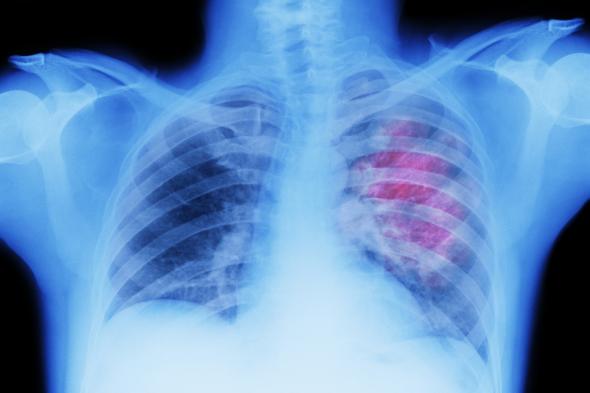

Radiografía de un tumor en el pechoGetty Images